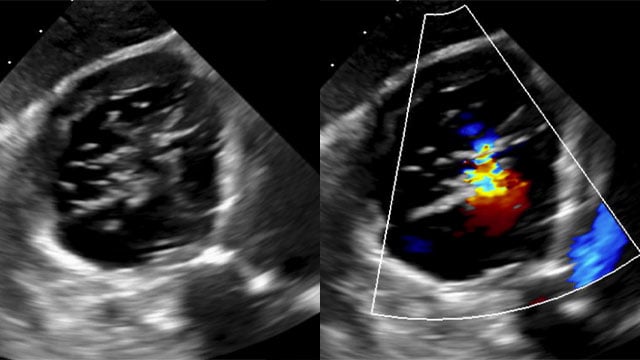

Severe MR in a high-risk patient with a suboptimal anatomy for M-TEER: what other options can we find?

Multimodality imaging reveals fibro-calcific leaflet disease, restricted motion, and a short posterior leaflet, making him a suboptimal candidate for M-TEER and prompting consideration of transcatheter mitral valve replacement. How would you treat?